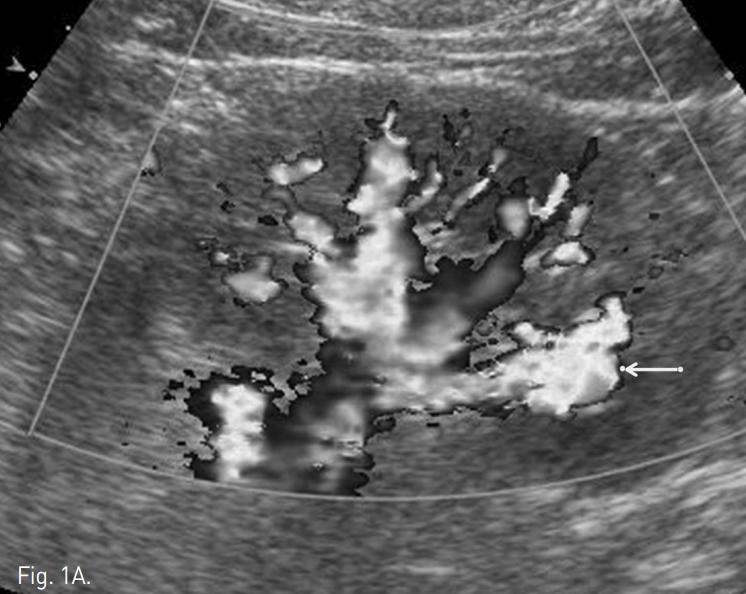

초음파에서 왼쪽 신장 하부에 1.3cm 크기의 낭성병변이 있으며, 내부에 mixed doppler signal이 관찰됨(Fig. 1A). 복부 CT에서도 동일한 위치에 혈관과 동일한 조영증강 양상을 보이는 1.7×1.3cm 크기의 혈관성 종괴가 있음(Fig. 1B).

Fig. 1

Renal doppler US and abdominal CT show a vascular mass suggesting nidus of AVM in lower pole of left kidney(arrow)